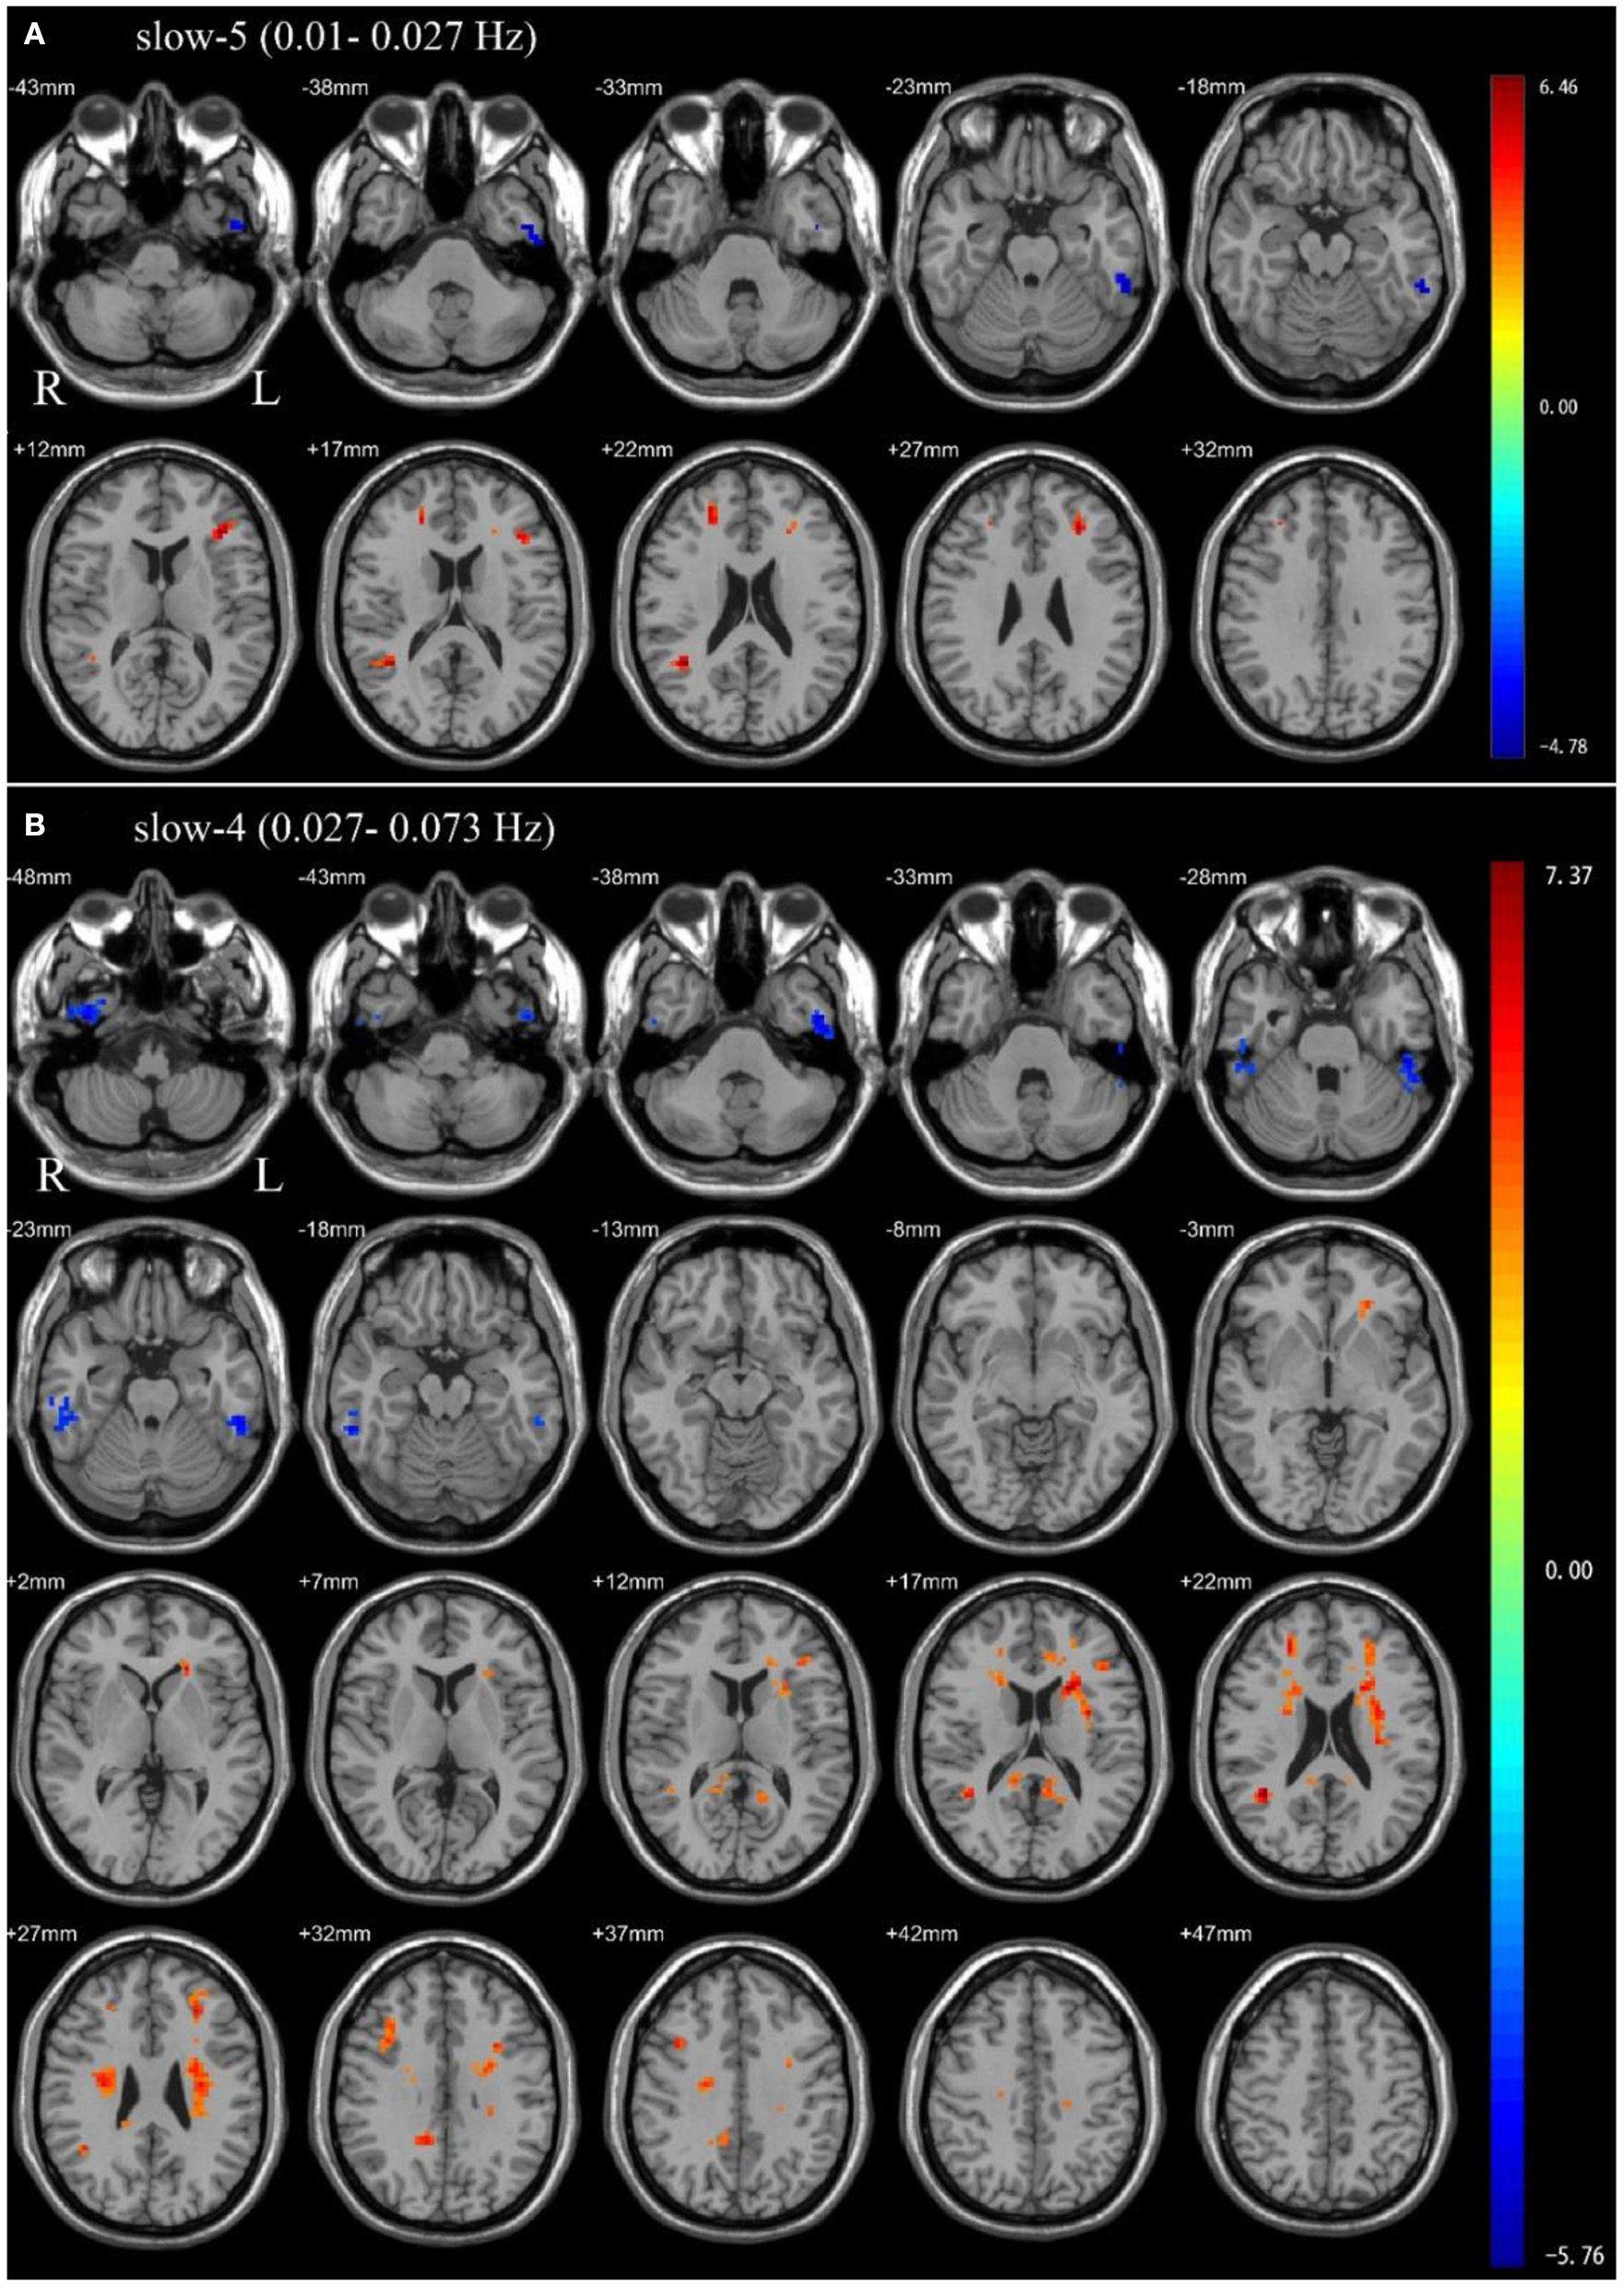

In the slow-5 frequency band, OSA patients showed significantly decreased ALFF in the left inferior temporal gyrus, and significantly increased ALFF in the left middle frontal gyrus, left inferior frontal gyrus, triangular part, right superior frontal gyrus, dorsolateral, right middle temporal gyrus compared to HC (Table 2 and Figure 1).

Figure 1

Independent sample t-test between health control groups and pre-CPAP OSA patients: (A) slow-5 frequency band (0.01–0.027 Hz). (B) slow-4 frequency band (0.027–0.073 Hz). Results were reported at voxel-level p < 0.001 and cluster-level p < 0.05, GRF corrected.

In the slow-4 frequency band, compared to HC, OSA patients showed significantly decreased ALFF in the bilateral inferior temporal gyrus, and significantly increased ALFF in the left precuneus, right posterior cingulate gyrus, right median cingulate, right middle temporal gyrus, right inferior frontal gyrus, opercular part, left middle frontal gyrus, left inferior frontal gyrus, triangular part (Table 2 and Figure 1).